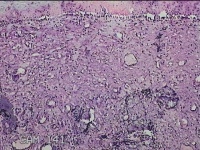

宫颈锥切物

女

31岁

宫颈上皮内瘤变

妇检发现宫颈CIN2 2个月。

灰白暗红色组织2.8x1.8x0.3cm一块,表面糜烂,切面灰白暗红色,质软。

所提供图片不具有诊断价值。

为什么不拍鳞状上皮呢?